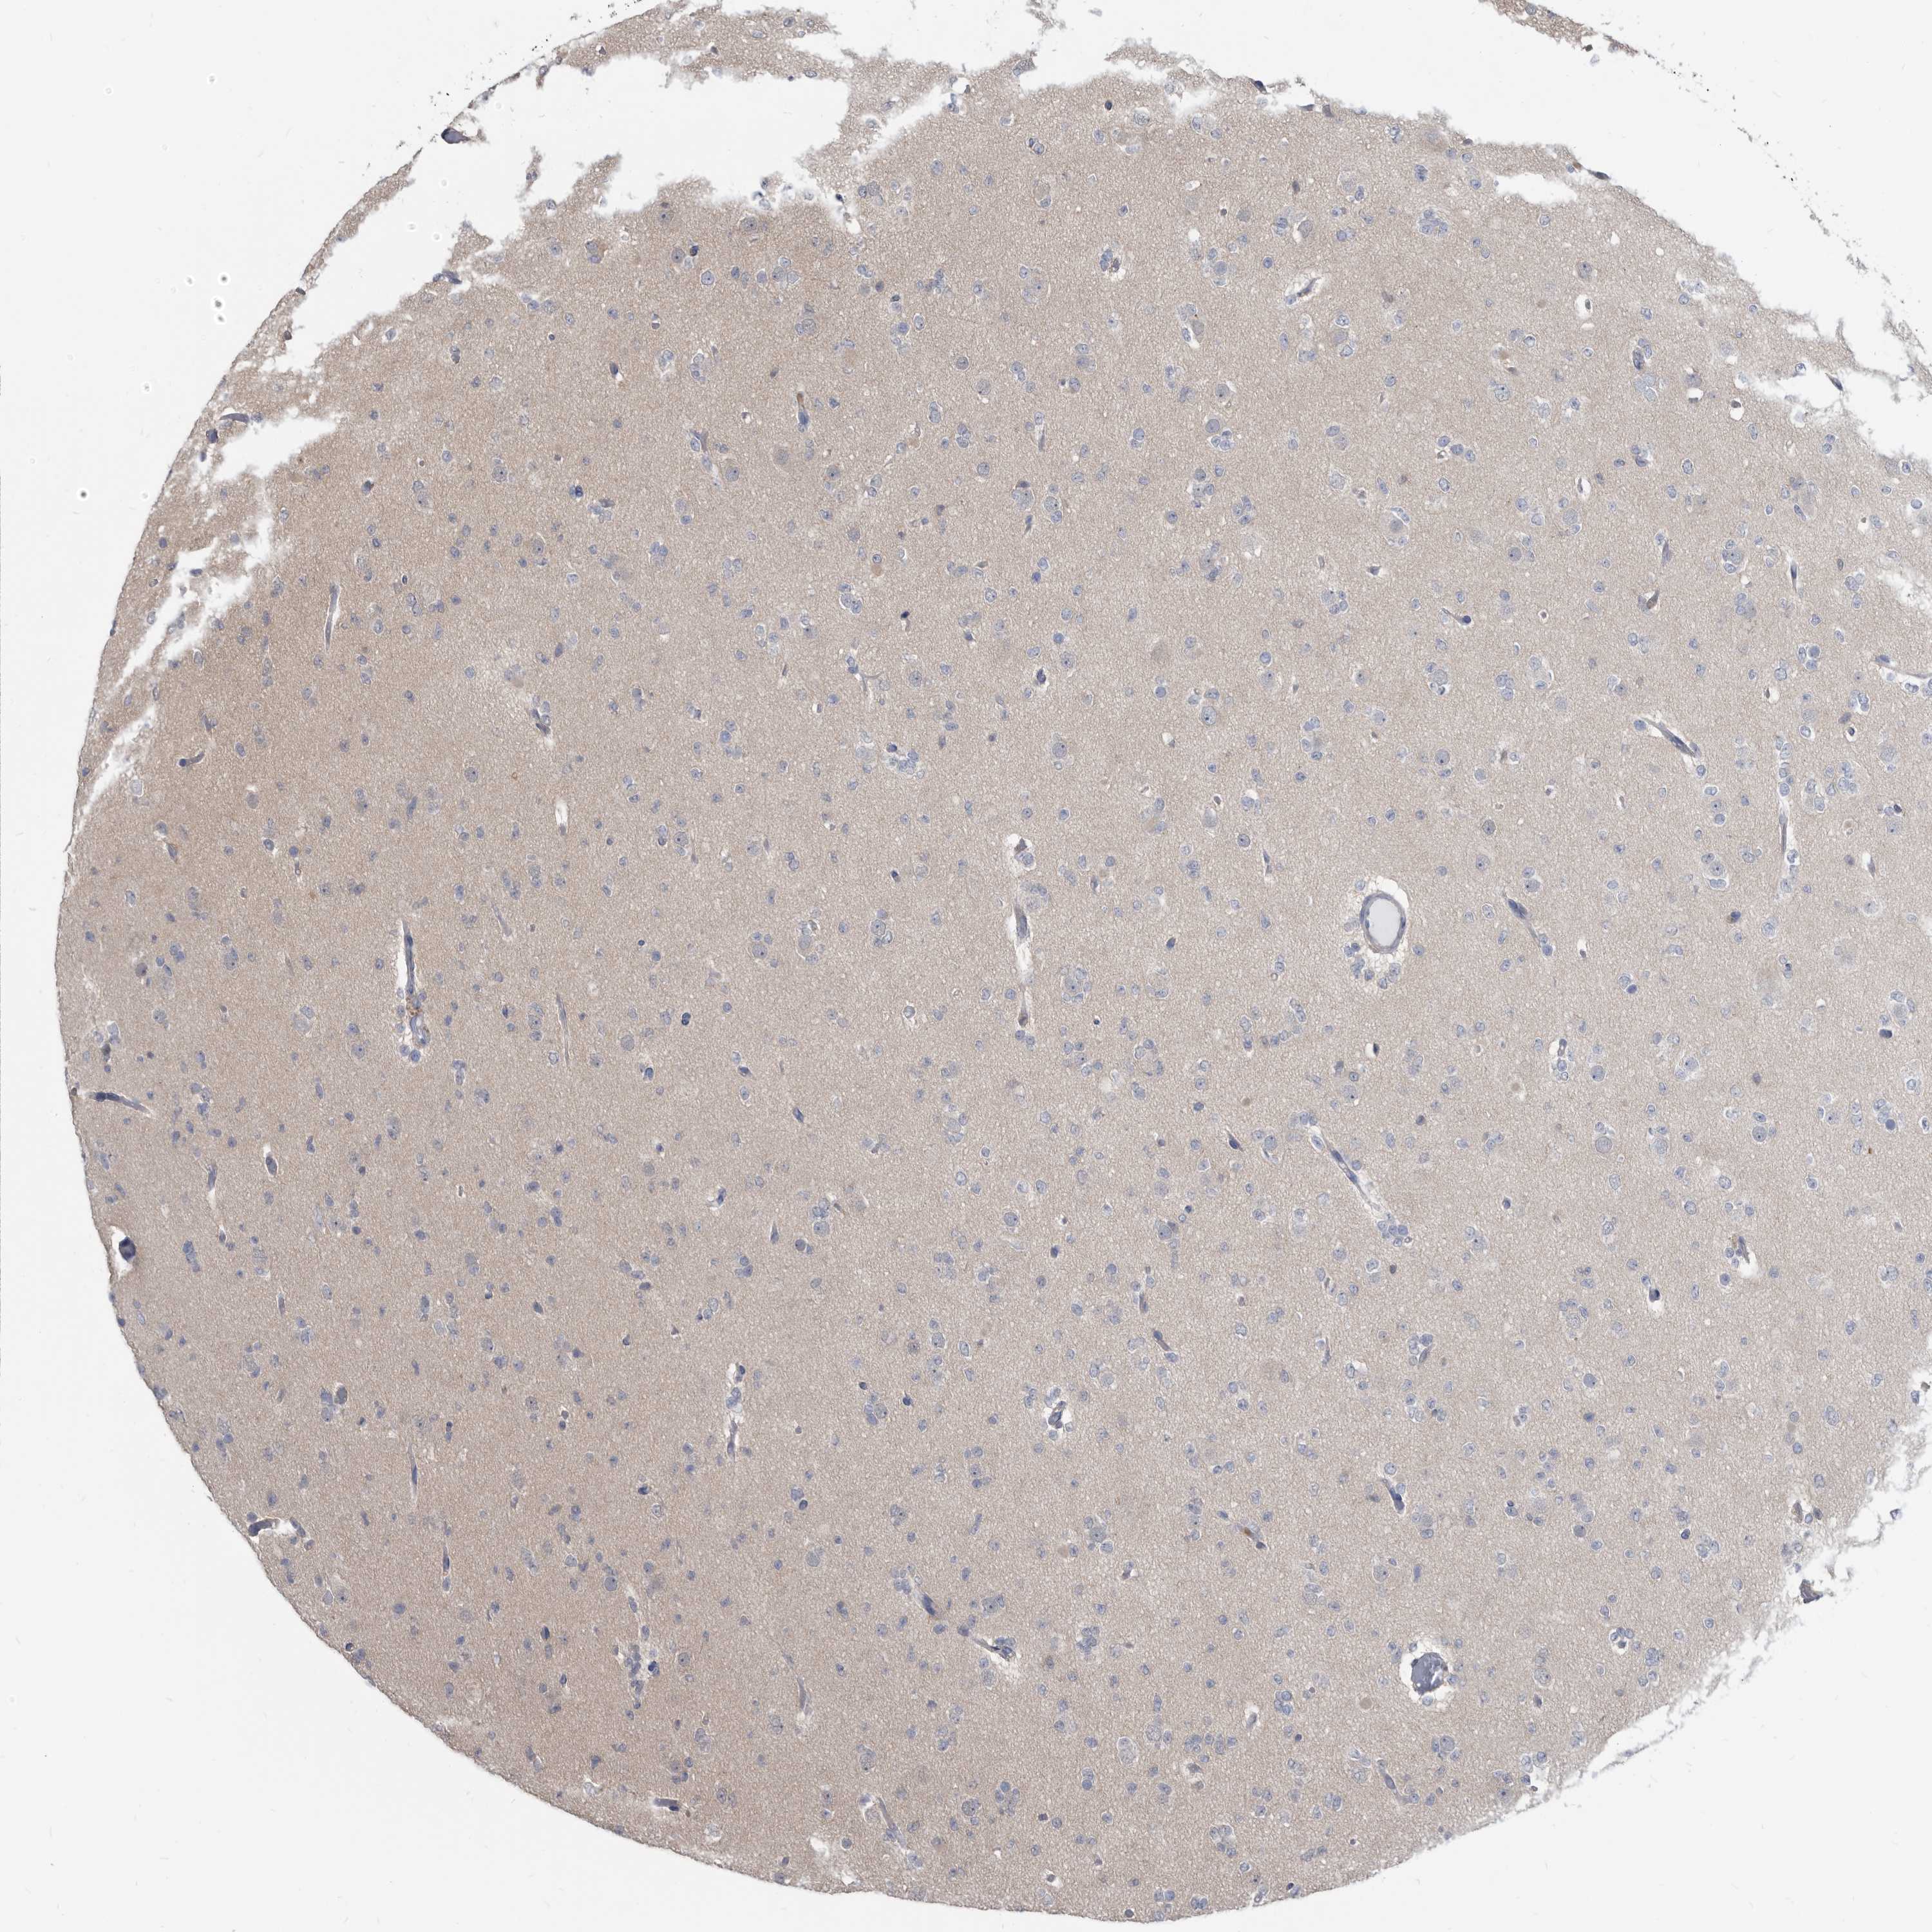

GLIOMA - Protein expressioni

A mouse-over function shows sample information and annotation data. Click on an image to view it in a full screen mode. Samples can be filtered based on level of antibody staining by selecting one or several of the following categories: high, medium, low and not detected. The assay and annotation is described here.

Note that samples used for immunohistochemistry by the Human Protein Atlas do not correspond to samples in the TCGA dataset.

Antibody stainingi

Antibody staining in the annotated cell types in the current human tissue is reported as not detected, low, medium, or high, based on conventional immunohistochemistry profiling in selected tissues. This score is based on the combination of the staining intensity and fraction of stained cells.

Each image is clickable and will lead to virtual microscopy that enables deeper exploration of all samples and also displays staining intensity scores, fraction scores and subcellular localization as well as patient and tissue information for each sample.

Antibody HPA029700

Antibody HPA029701

Antibody HPA029702

Antibody HPA029703

Staining

High

Medium

Low

Not detected

Intensity

Strong

Moderate

Weak

Negative

Quantity

>75%

75%-25%

<25%

None

Location

Nuclear

Cytoplasmic/membranous

Cytoplasmic/membranous,nuclear

Glioma, malignant, High grade

Glioma, malignant, Low grade

Glioblastoma, NOS